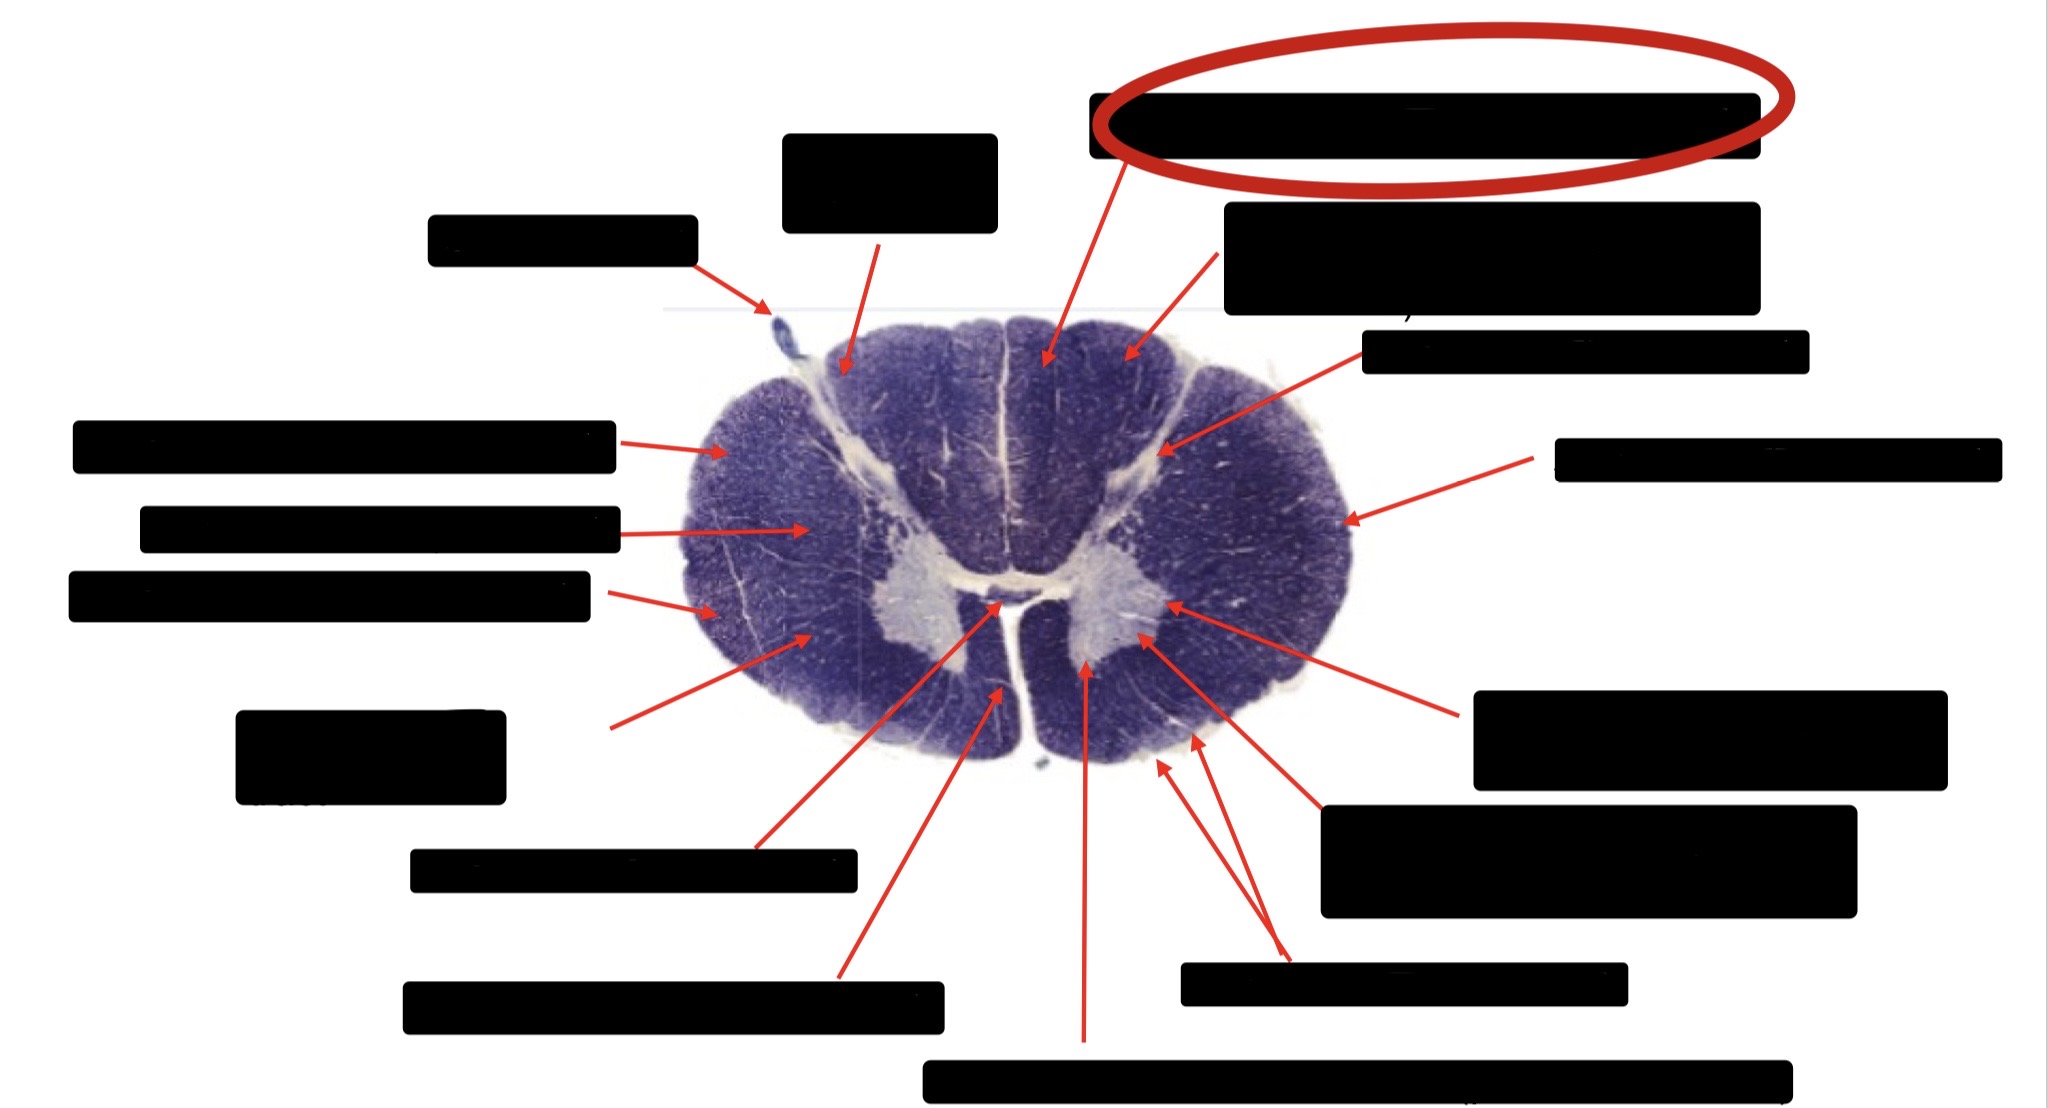

Spinothalmic Tract

Central Canal

Posterior Column (Fasciculus Gracilis)

Large Fiber Entry Zone

Lissaeur’s Tract & Small Fiber Entry Zone

Substantia Gelatinosa

Lateral Corticospinal Tract

Ventral Root Fibers

Anterior Horn Motor Neurons

Anterior Medial Fissure

Dorsal Rootlet

Posterior Spinocerebellar Tract

Anterior Spinocerebellar Tract

Posterior Column (Fasciculus Cuneatus)

Anterior Horn Motor Neurons (Distal Muscles)

Anterior Horn Motor Neurons (Proximal Muscles)

Anterior Corticospinal Tract